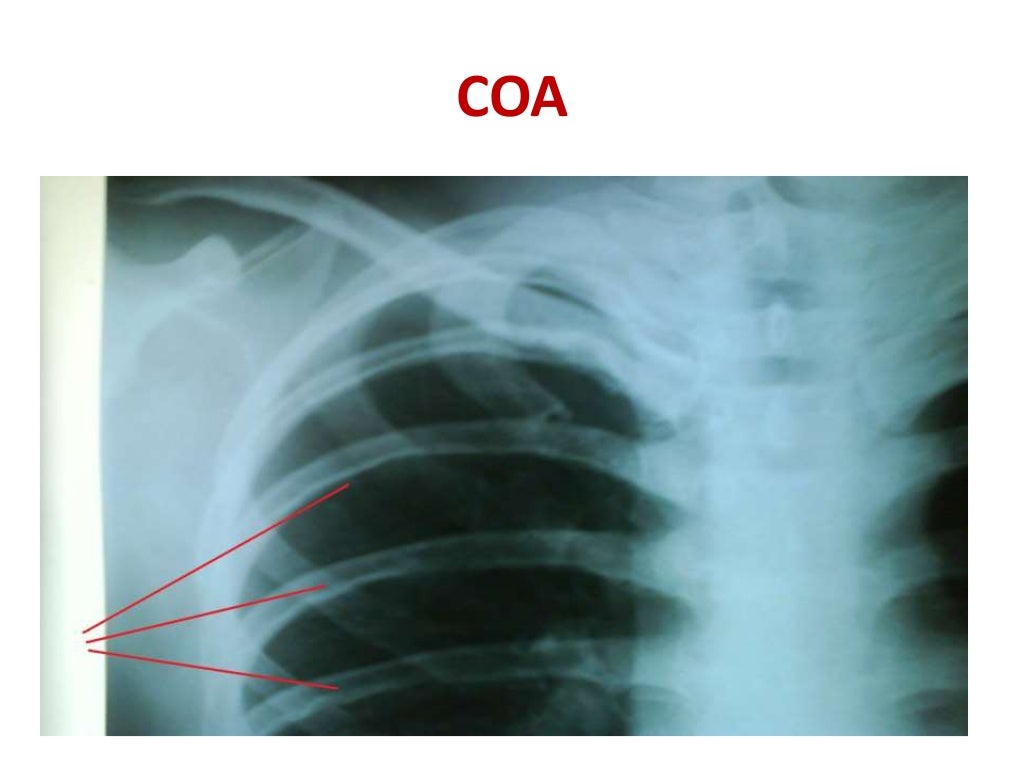

Coarctation of the Aorta Rib Notching Definition Acute rib infections are seen as focal areas of bone destruction, whereas chronic infections may manifest as periosteal reaction or a bone sequestrum. Normal variants and abnormalities of the ribs are frequently encountered on chest radiographs. Rib notching are deformities that affect the upper surface of the rib, the lower surface of the rib (roesler’s sign), or both. This article. Rib Notching Definition.

Coarctation of the Aorta wikiRadiography Rib Notching Definition Acute rib infections are seen as focal areas of bone destruction, whereas chronic infections may manifest as periosteal reaction or a bone sequestrum. Normal variants and abnormalities of the ribs are frequently encountered on chest radiographs. Rib notching are deformities that affect the upper surface of the rib, the lower surface of the rib (roesler’s sign), or both. This article. Rib Notching Definition.

Inferior rib notching, COA Diagnostic imaging, Radiography, Movie posters Rib Notching Definition Rib notching are deformities that affect the upper surface of the rib, the lower surface of the rib (roesler’s sign), or both. Normal variants and abnormalities of the ribs are frequently encountered on chest radiographs. Acute rib infections are seen as focal areas of bone destruction, whereas chronic infections may manifest as periosteal reaction or a bone sequestrum. This article. Rib Notching Definition.